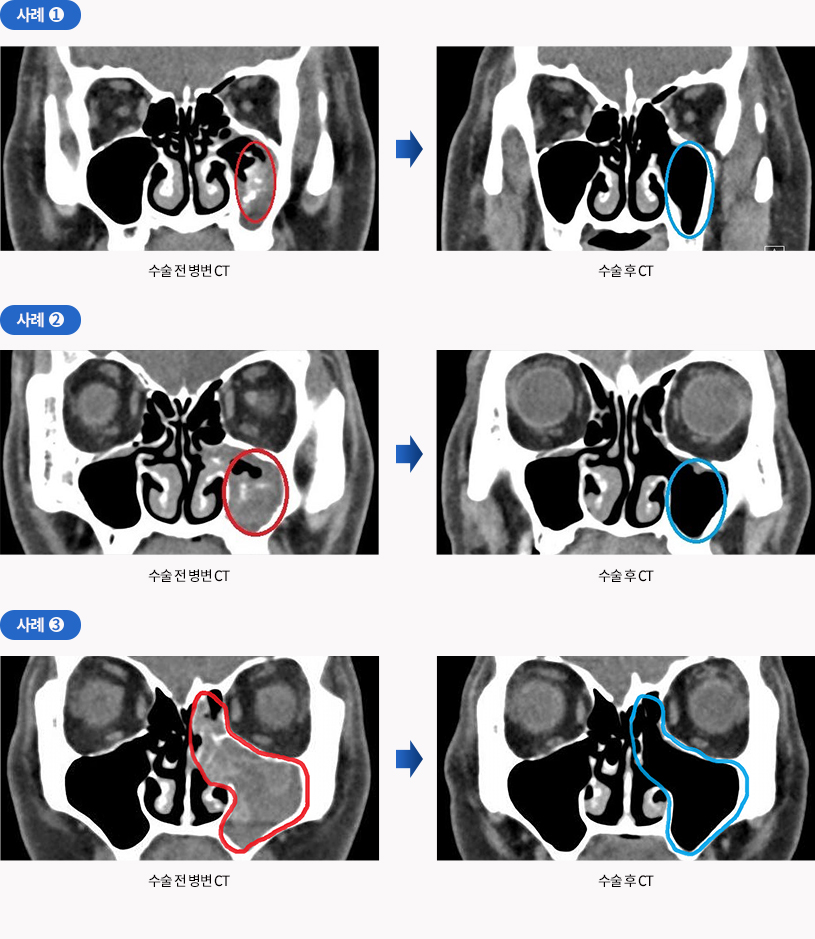

충분한 기간 동안 약물 치료받았는데도 호전이 없는 경우에는 수술적 치료(내시경수술)를 받아야 합니다. 약물 치료에 호전이 없는 경우는 물혹을 동반한 경우가 많으므로 수술을 통하여 물혹을 제거하고 코 안에 자연공을 넓혀줍니다. 차있는 농을 깨끗이 씻어내어 수술 후에는 코 안에 환기가 잘되고 섬모운동이 개선되어 농이 고이지 않도록 해줍니다. 때로는 곰팡이(진균)에 의한 축농증이 확인되기도 하는데, 이 경우 반드시 수술을 통한 완전 제거가 필요합니다.

진균성 부비동염의 수술 사례